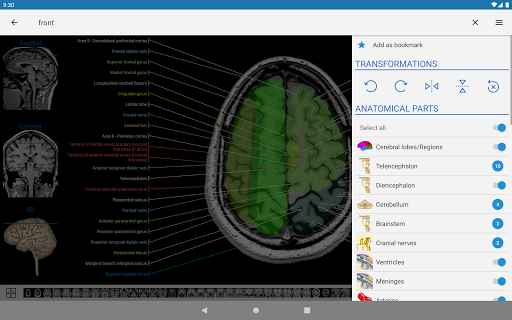

-The pins mode have a new behaviour allowing you to follow an anatomical structure much more easily

- You can now hide structures one by one (new button inside the description popup) and display them again in the right menu